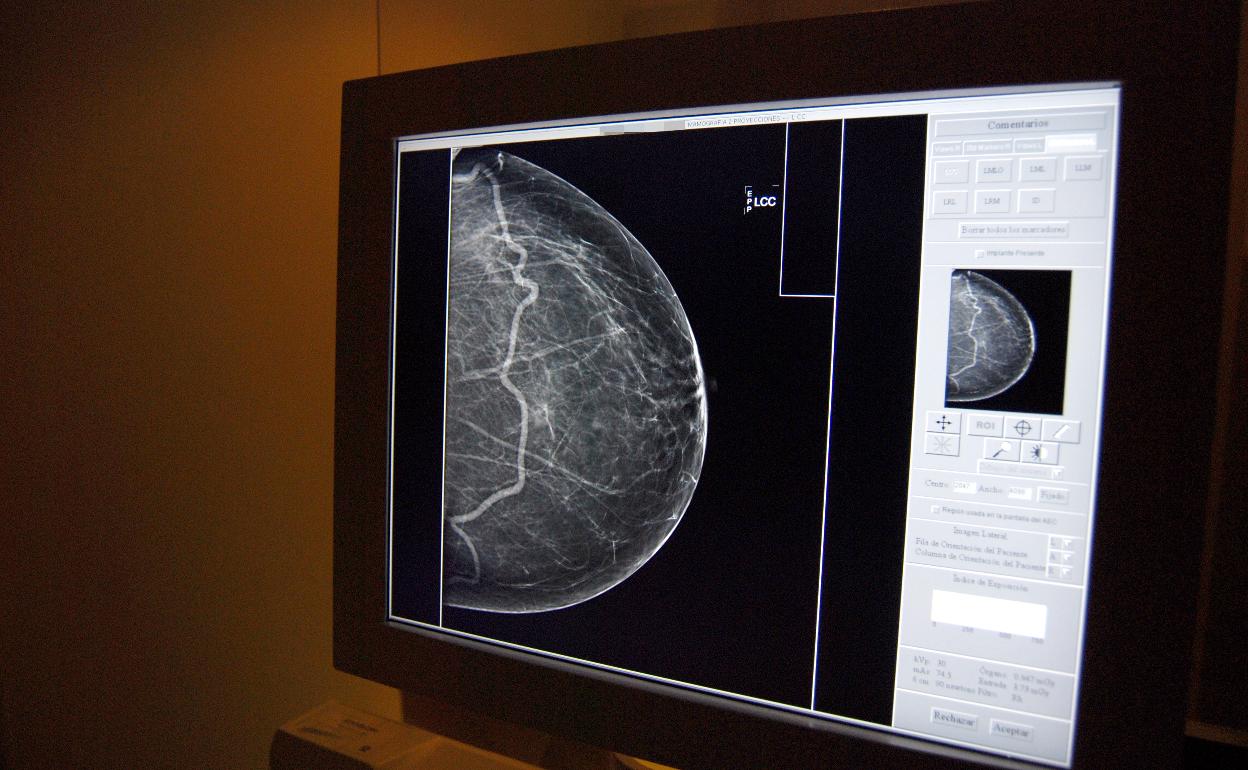

El Centro de Investigaciones Biomédicas de la Universidad de Castilla-La ancha y la Unidad de Investigación del Hospital Universitario de Albacete han demostrado que la combinación de dos fármacos ofrece un alto potencial como tratamiento del cáncer de mama subtipo HER2, uno de los más agresivos.